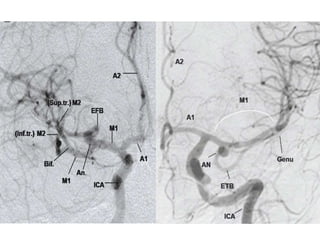

Angiographic Sylvian Point (ASP)

• It is the most medial point where the last

cortical MCA branch (usually the angular

artery) turns inferiorly to exit the sylvian

fissure.(On AP view)

• This point approximates the apex of the insula

and represents the posterior limit of the

lateral cerebral sulcus.

Sylvian triangle (angiographic)

• The superior insular line ( A line tangent to the

tops of the insular loops),

• Main MCA trunk ( forms the posterior inferior

margin of the triangle)

• Most anterior branch of the ascending frontal

complex ( forms the anterior border of the

triangle)

• It is seen in lateral view and serves as angiographic

landmark for localizing supratentorial masses.

• Round shift = Frontal lesion anterior to coronal

suture

• Square shift = Lesion behind foramen of Monro

in lower half of hemisphere

• Distal shift = Posterior to coronal suture in

upper half of hemisphere

• Proximal shift = Basifrontal lesion / anterior

middle cranial fossa including anterior temporal

lobe

Angiographic Sylvian Point(ASP) • It is the most medial point where the last cortical MCA branch (usually the angular artery) turns inferiorly to exit the sylvian fissure.(On AP view) • This point approximates the apex of the insula and represents the posterior limit of the lateral cerebral sulcus.

Sylvian triangle (angiographic) •The superior insular line ( A line tangent to the tops of the insular loops), • Main MCA trunk ( forms the posterior inferior margin of the triangle) • Most anterior branch of the ascending frontal complex ( forms the anterior border of the triangle) • It is seen in lateral view and serves as angiographic landmark for localizing supratentorial masses.

• Round shift= Frontal lesion anterior to coronal suture • Square shift = Lesion behind foramen of Monro in lower half of hemisphere • Distal shift = Posterior to coronal suture in upper half of hemisphere • Proximal shift = Basifrontal lesion / anterior middle cranial fossa including anterior temporal lobe